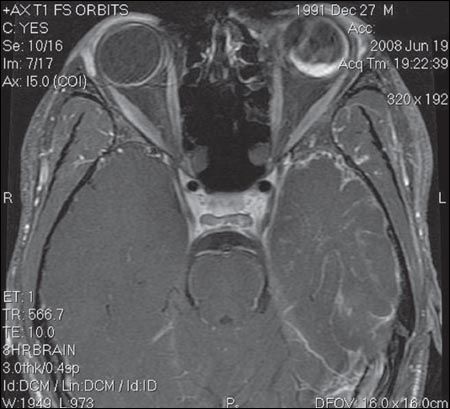

Ultrasonogram of the orbit revealed choroidal hemorrhage in the left orbit with overlying retinal detachment. Patient's MRI scan is shown.

The MRI scan confirmed the ultrasonographic findings and also showed atrophy of the cortex on the left side with prominent overlying venous malformation. A diagnosis of Sturge-Weber syndrome was made on the basis of the patient's clinical appearance and radiological findings.